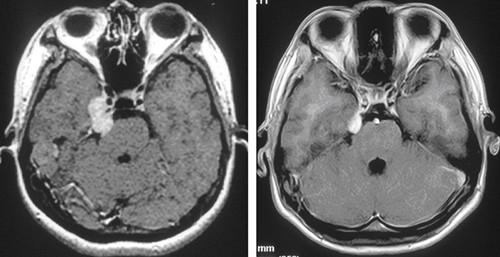

三叉神經(jīng)鞘瘤給患者健康造成很大的危害,出現(xiàn)包括頭痛、單側面肌痙攣、聽覺障礙、局灶性癲癇、偏癱、步態(tài)異常、耳痛等癥狀。所以一定要及時去醫(yī)院進行檢查治療。

(2)分組 五組分別為后顱窩腫瘤;三叉神經(jīng)節(jié)腫瘤;啞鈴狀和幕下前方的腫瘤;外周分支的神經(jīng)瘤;多顱窩的腫瘤(顱中窩和顱后窩,或顱中窩、顱后窩及顱外)。約36%~59%的三叉神經(jīng)鞘瘤累及多個顱窩。